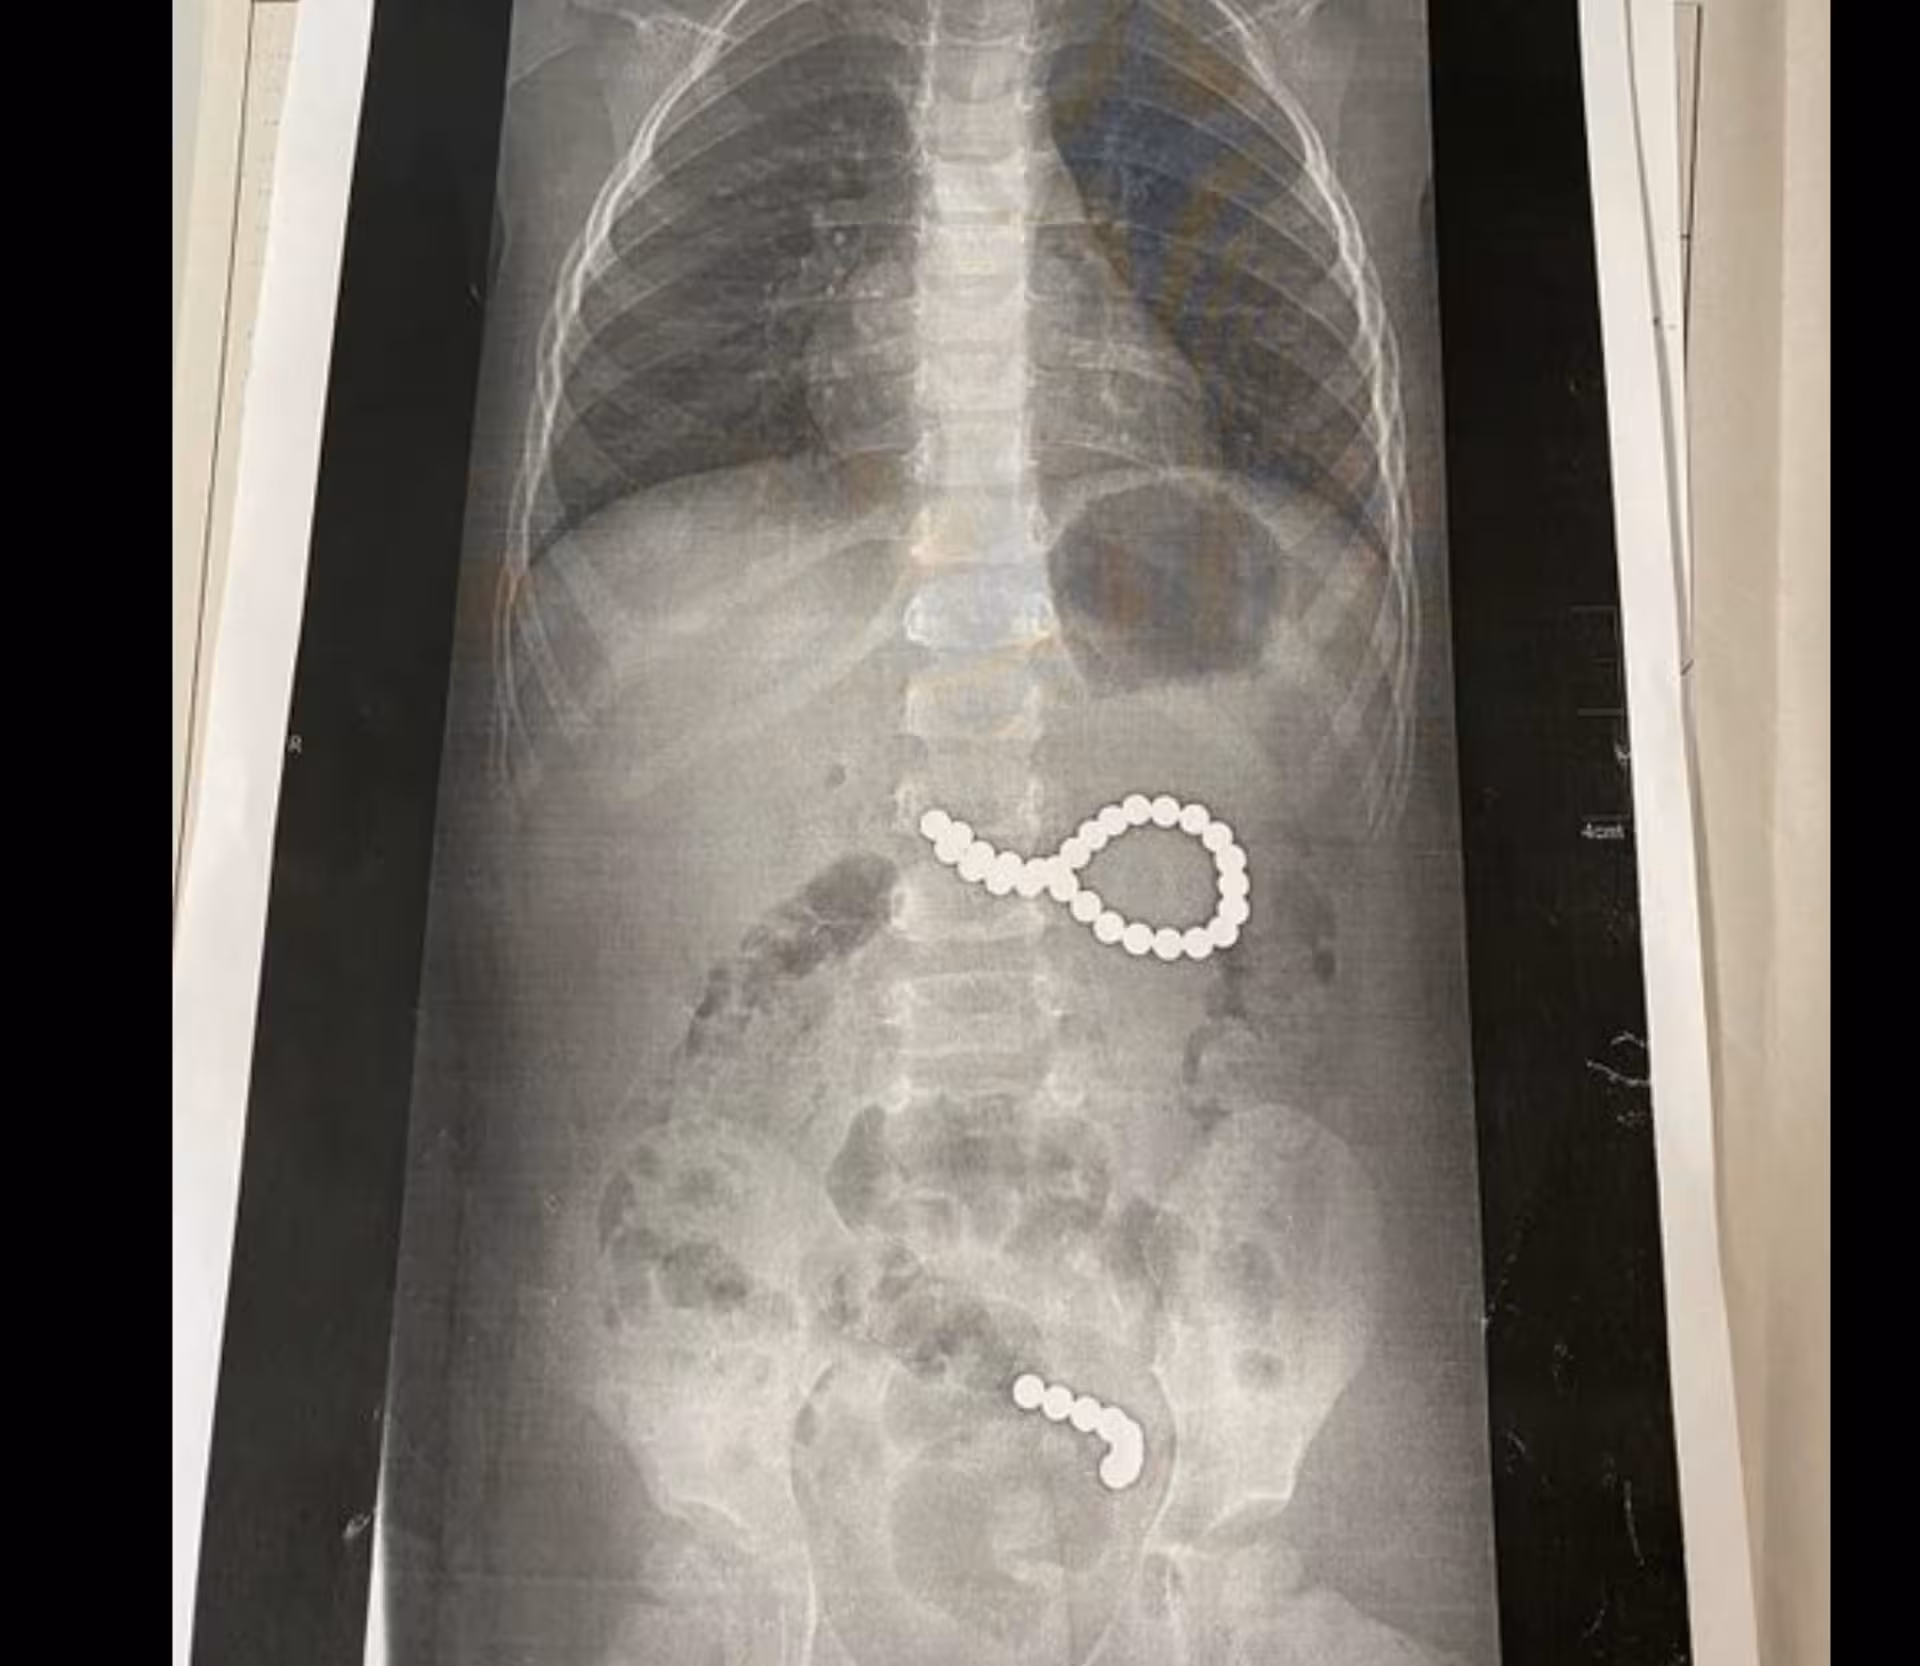

У суботу, 6 вересня, до львівської обласної дитячої лікарні ОХМАТДИТ госпіталізували дворічну дівчинку з Дрогобицького району, яка проковтнула 36 магнітних кульок від конструктора. Про це пише "Zaxid.net".

Дев’ять кульок під дією магнітного поля утворили ланцюжок і потрапили в кишківник, ще 27 кульок утворили неправильне коло і потрапити в кишківник не могли. Дівчинку довелося терміново оперувати.

«Дев’ять кульок, які дитина проковтнула у п’ятницю, утворили ланцюжок, бо було сильне магнітне поле. І вони пройшли зі шлунка в тонкий кишківник. А ті 27 магнітних кульок, які дитина проковтнула у суботу, утворили неправильне коло і їх терміново треба було діставати. Кульки були діаметрои 4 мм, найвірогідніше, з якогось конструктора», — каже Оксана Горбач.